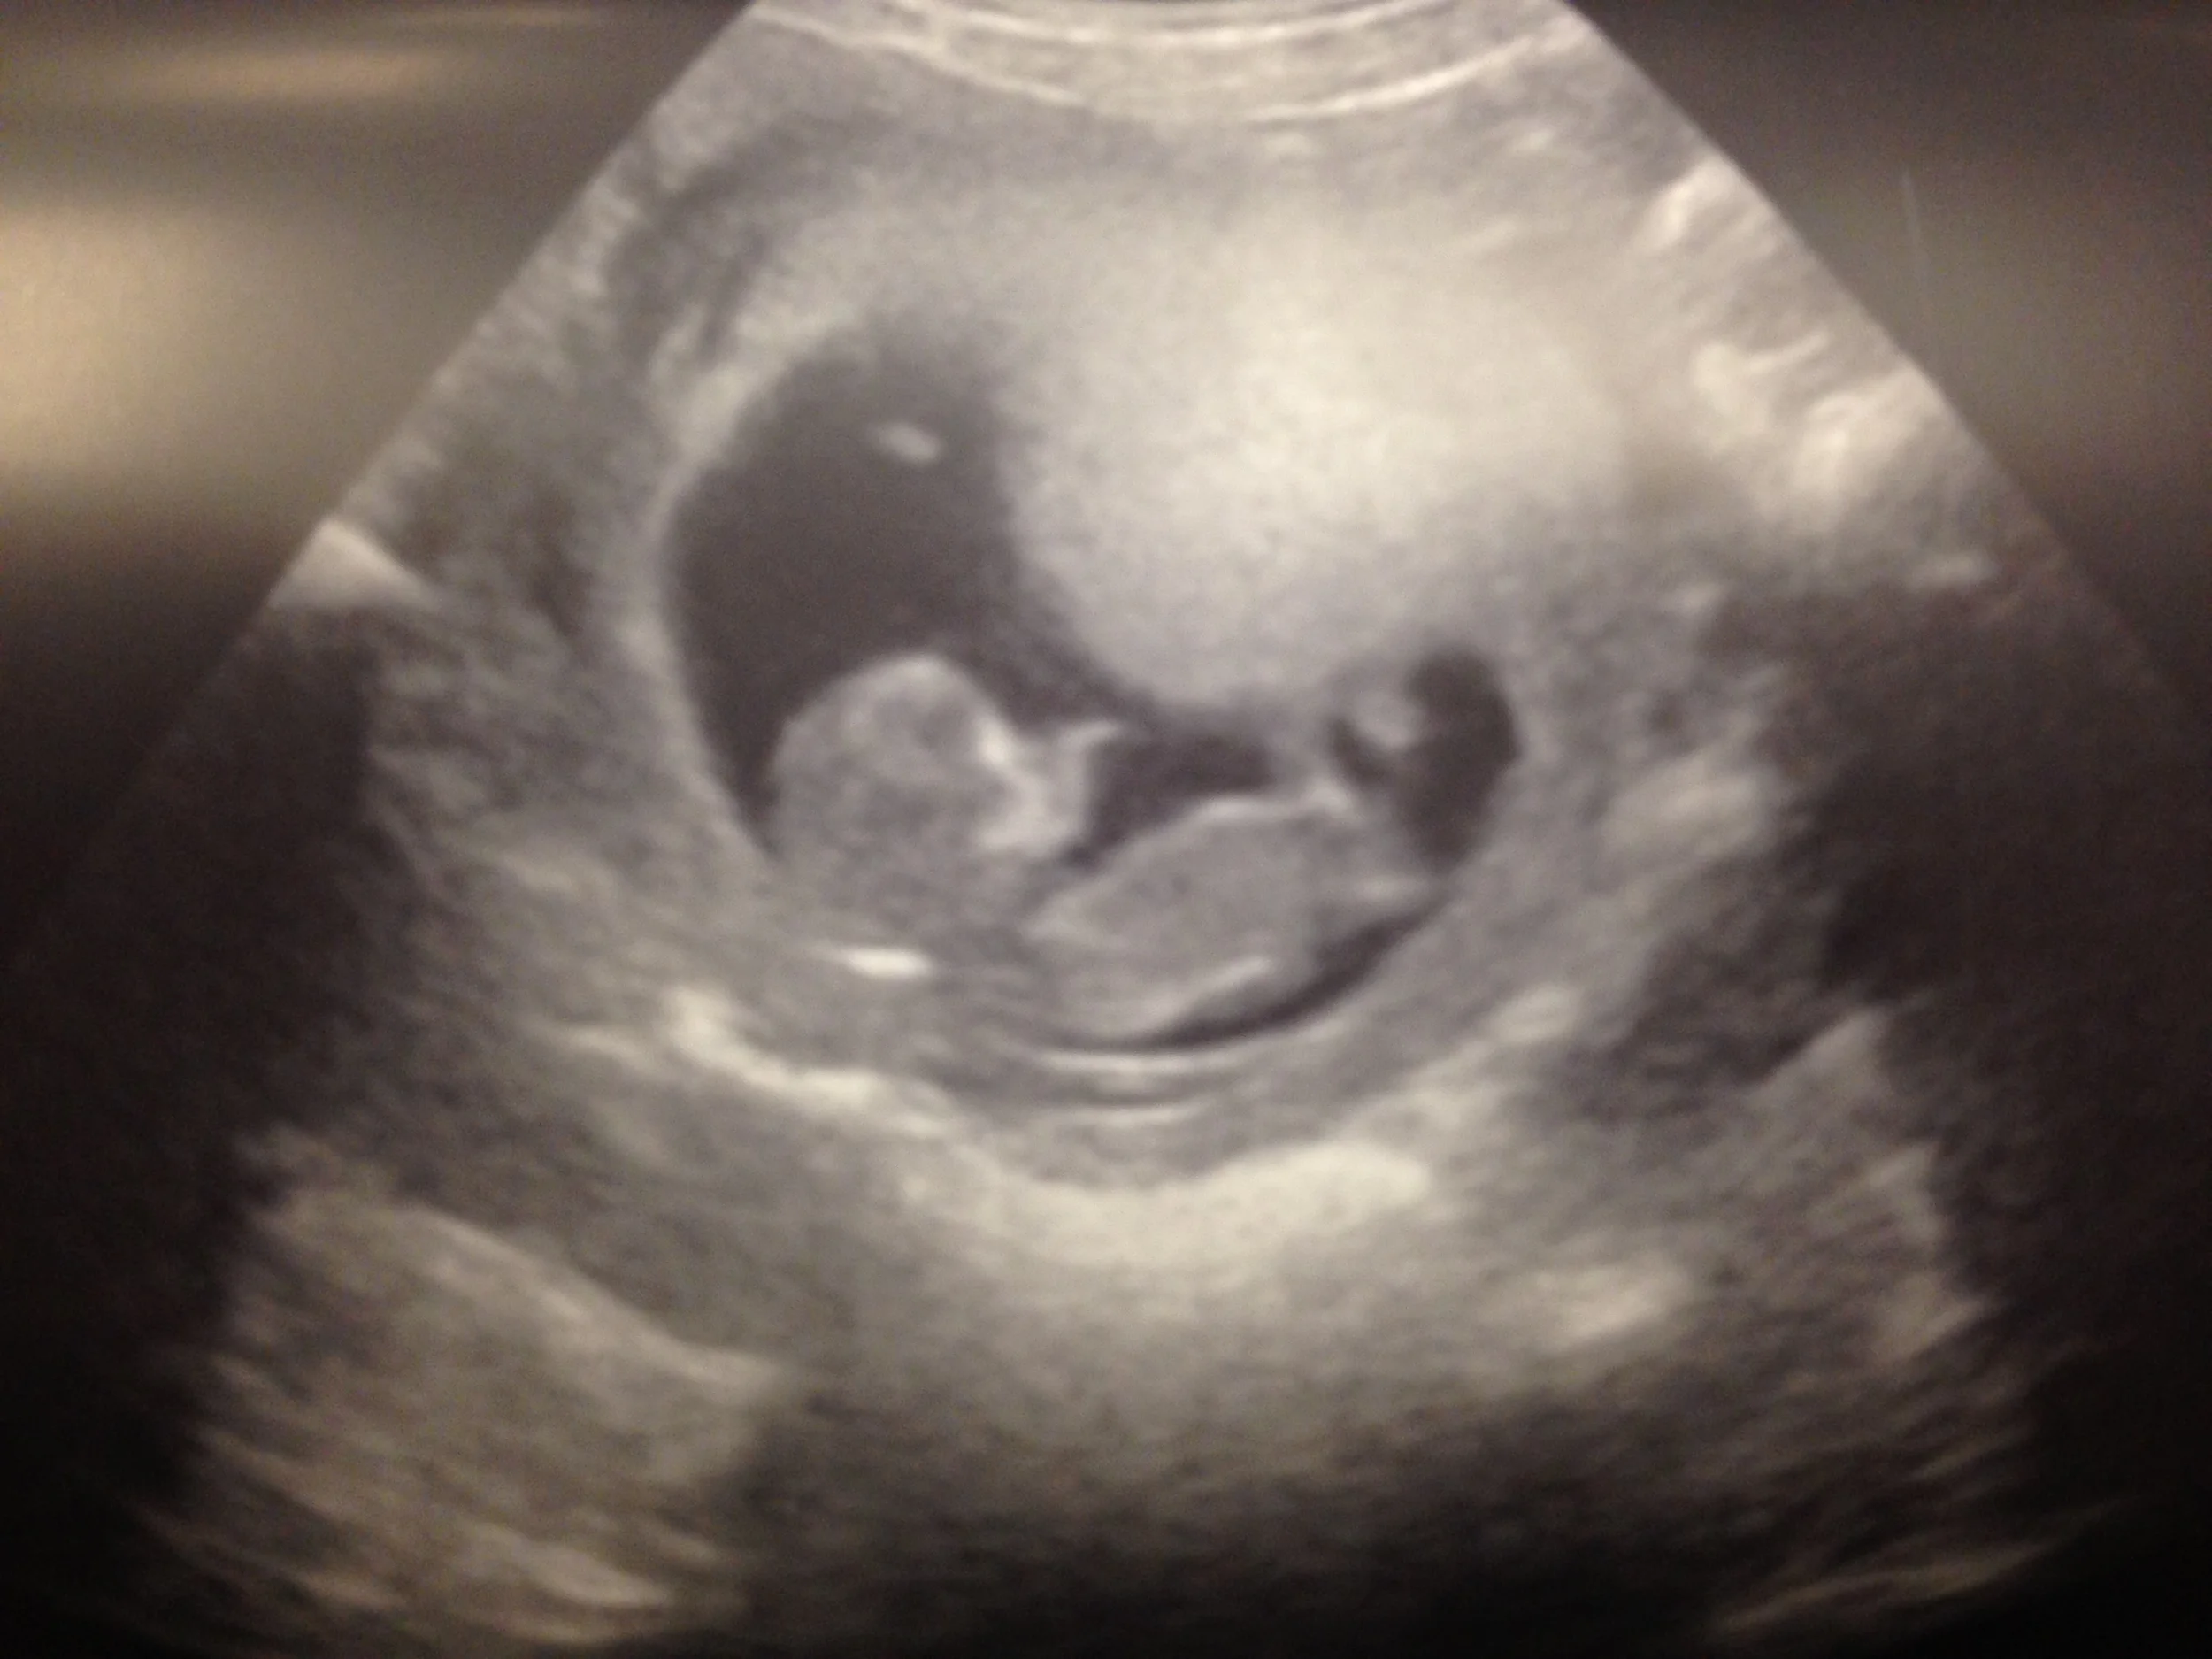

August 20, 2015: 9wks1day - Baby has a heartbeat and the urge to dance apparently.

Thank you for the extreme outpouring of support in the last couple of days. We are so happy to share this with our friends and family and so full of gratitude for this chance to pick up anew and love this baby. Several of you have asked for pictures of my "bump." Y'all, this is my first pregnancy and I have strong yogi-abs. So below are the pics...very underwhelming. If it wasn't for the ultrasound I would still be skeptical...

I mean, kinda. Only because that's normally super flat...9wks+3days